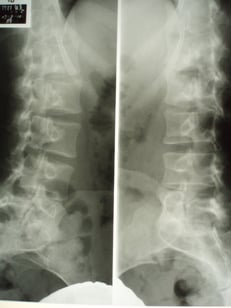

○ 脊椎分離症

中高生 大学生でスポーツを激しく休みなく続けていると背骨の関節分部の骨に疲労骨折がおこり

脊椎分症になっていることがあります。 怪しい症例はレントゲン検査をします。

脊椎分離には新しい新鮮なものと、陳旧性(過去に起きたもの)とがあり対応が違います。

鑑別が大切! 必要があれば直ぐに医師を紹介し適切な処置をします。

専門医師とネットワークを作っています。